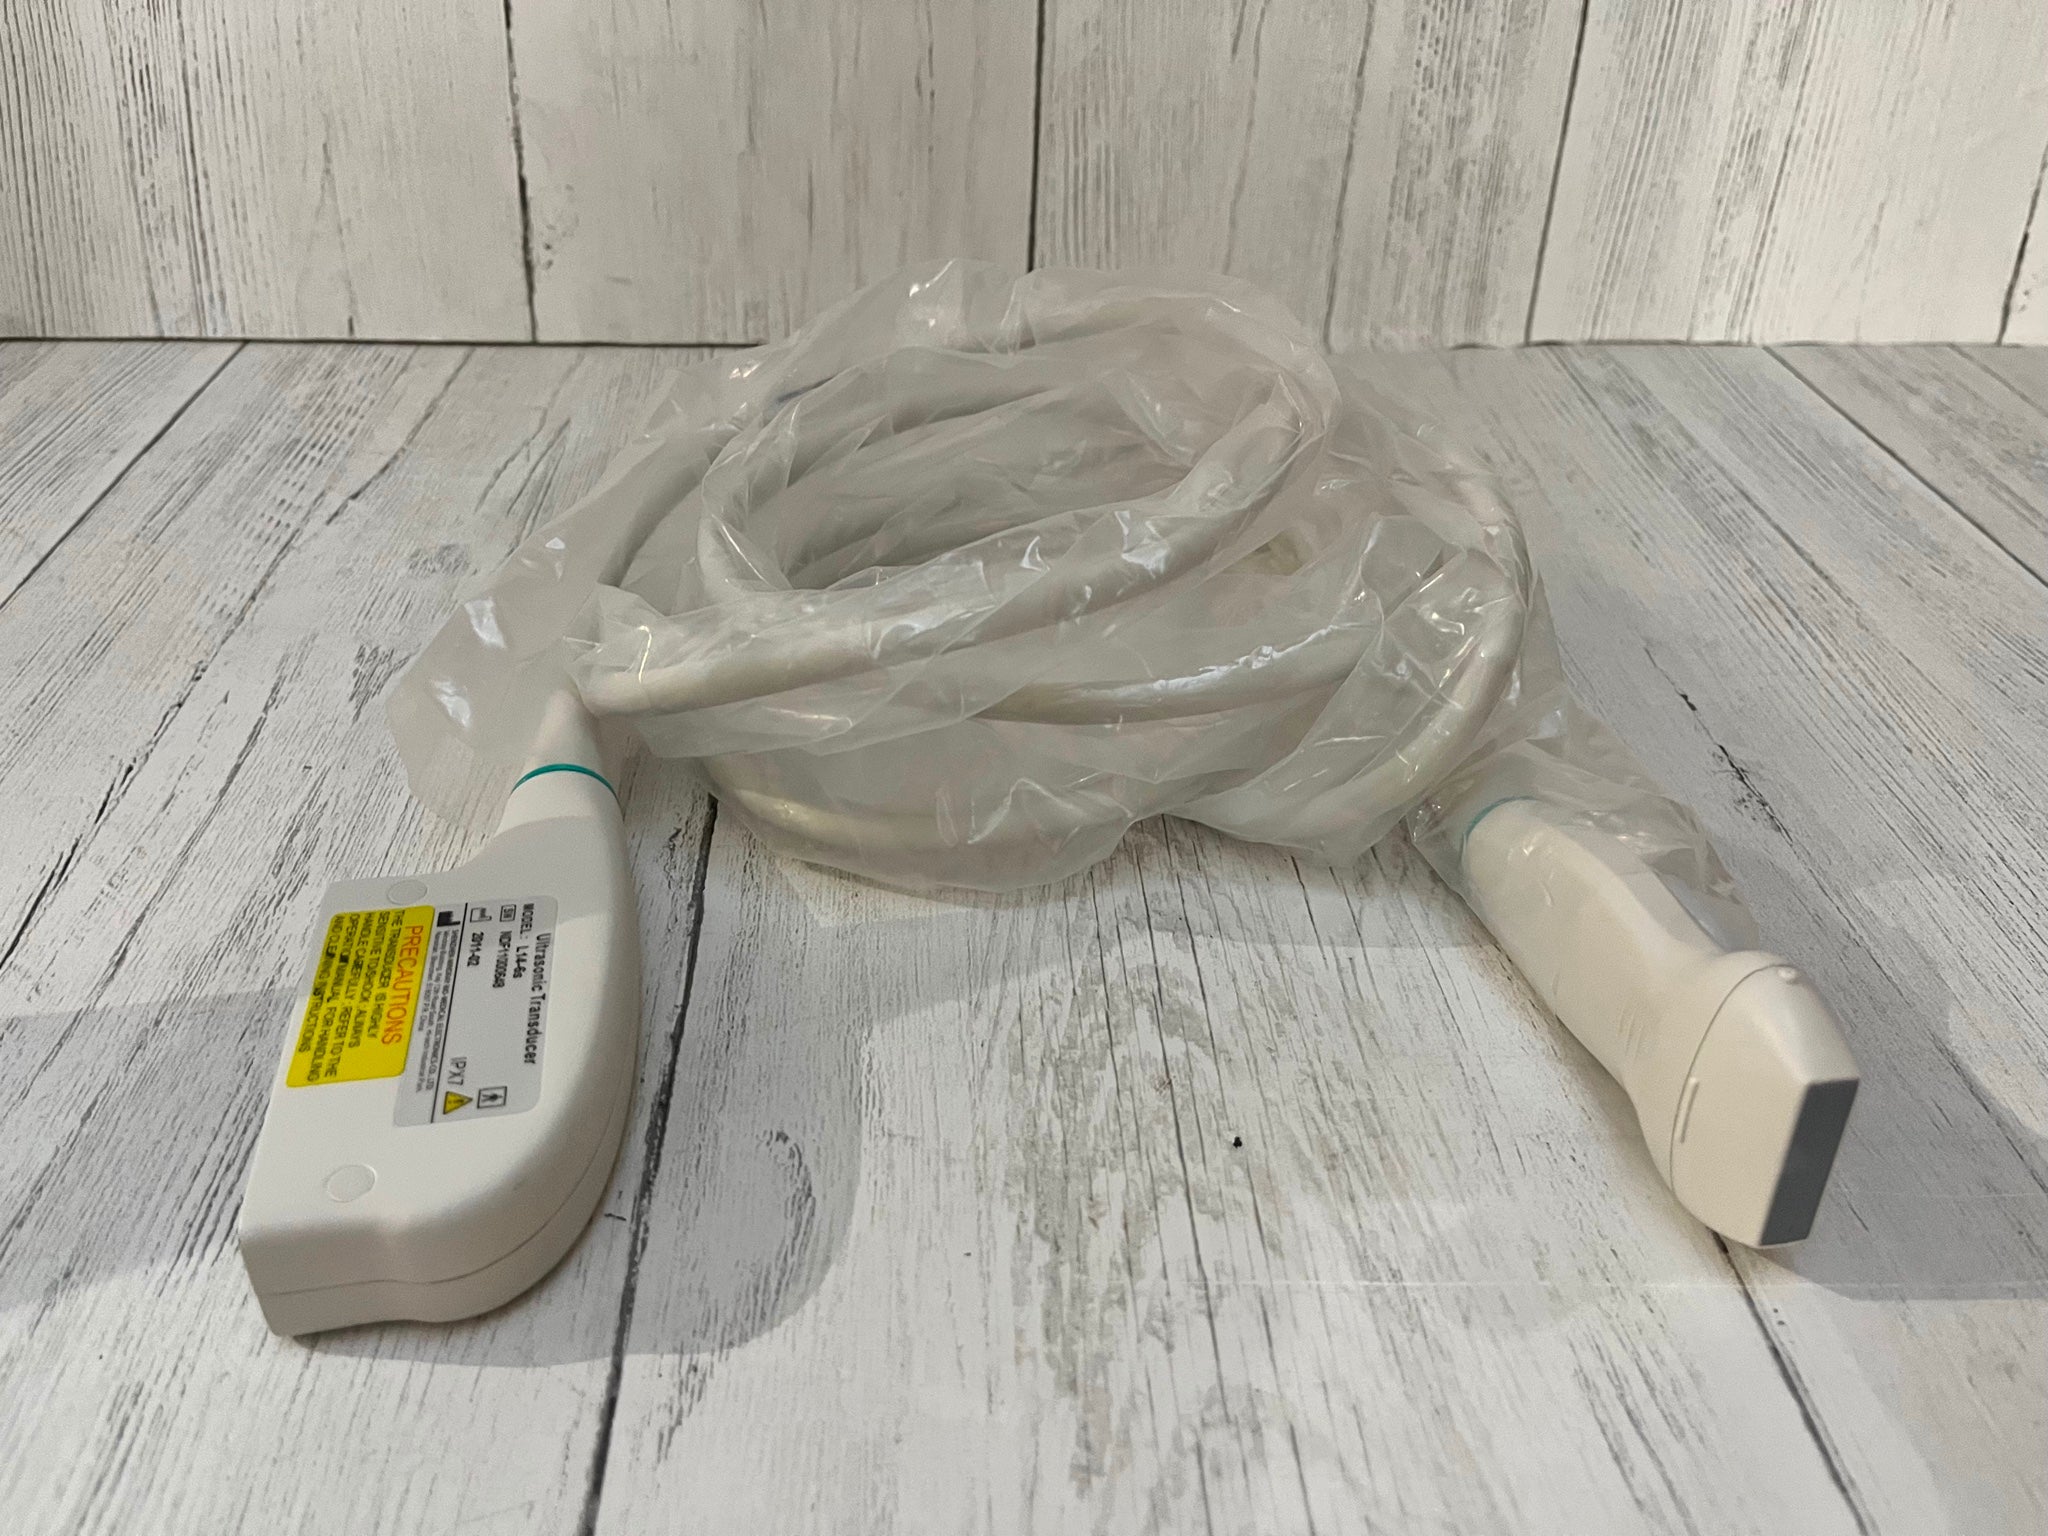

Digital Laptop External 3D Ultrasound Scanner+ Convex & Linear Probe 10" LCD CE 190891750662

Probe frequency: 2.5~10.0 MHz

probe connector: 1